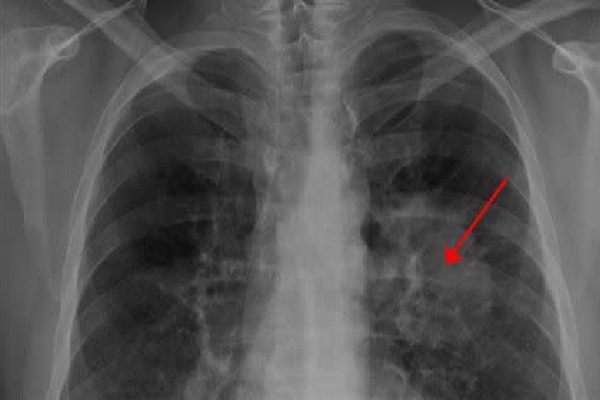

Ảnh minh họa